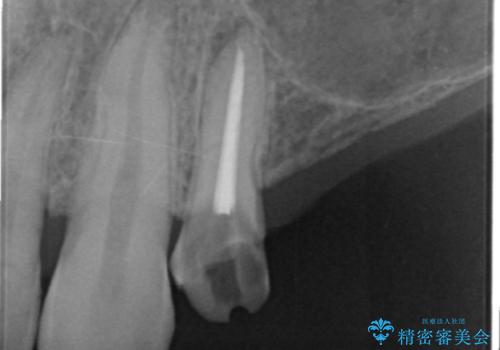

しっかりと造骨を行ったことでインプラント周囲には十分な量の骨が存在し安定したインプラント周囲環境を整えることができました。

残存している小臼歯も虫歯が大きく保存が難しいため抜去を行い造骨を含めたインプラント治療を行います。